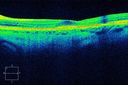

Plaquenil Toxicity - Bulls Eye Maculopathy1249 views70-year-old woman with systemic Lupus erythematosus and clotting problems. She was on the Plaquenil for about eight years and then off the Plaquenil for the last eight years because she developed macular toxicity. Although her vision was hazy, it was stable. Recent deceased vision left eye: OD 20/60, OS 20/100. IOP: OD 18, OS 19.